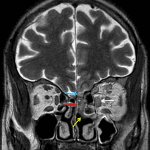

- T2 isointense to hypointense signal material in left ethmoid air cells extending into the olfactory recess as well as along the left superior and middle nasal turbinates with nonenhancement of the left middle turbinate

- This material appears to extend across the cribriform plate and along the floor of the left anterior cranial fossa with adjacent patchy T2 hyperintensity and enhancement in the left gyrus rectus

- Abnormal enhancement in the left pterygopalatine fossa

- Infiltrative enhancement in the intraconal and extraconal left orbit with an enlarged, T2 hyperintense left medial rectus muscle and abnormal circumferential enhancement of the left optic nerve sheath

- Left proptosis

- Engorged left superior ophthalmic vein which appears nonenhancing near the orbital apex with mild bulging of the lateral wall of the left cavernous sinus

- T1 signal hyperintensity in the bilateral globi pallidi

- Invasive fungal sinusitis

Findings are highly concerning for invasive fungal sinusitis spreading from left ethmoid air cells superiorly along the floor of the left anterior cranial fossa, laterally into the left orbit, and posteriorly into the left pterygopalatine fossa. Associated necrosis of the left middle turbinate, left medial rectus myositis, left optic perineuritis, left proptosis, and inferior left frontal cerebritis. No evidence of intracranial abscess. Recommend urgent ENT and neurosurgical evaluation.

Additionally, there are findings concerning for early left superior ophthalmic vein and left cavernous sinus thrombosis.

T1 signal hyperintensity in the bilateral globi pallidi, which is nonspecific but can be seen in the setting of hepatic failure.